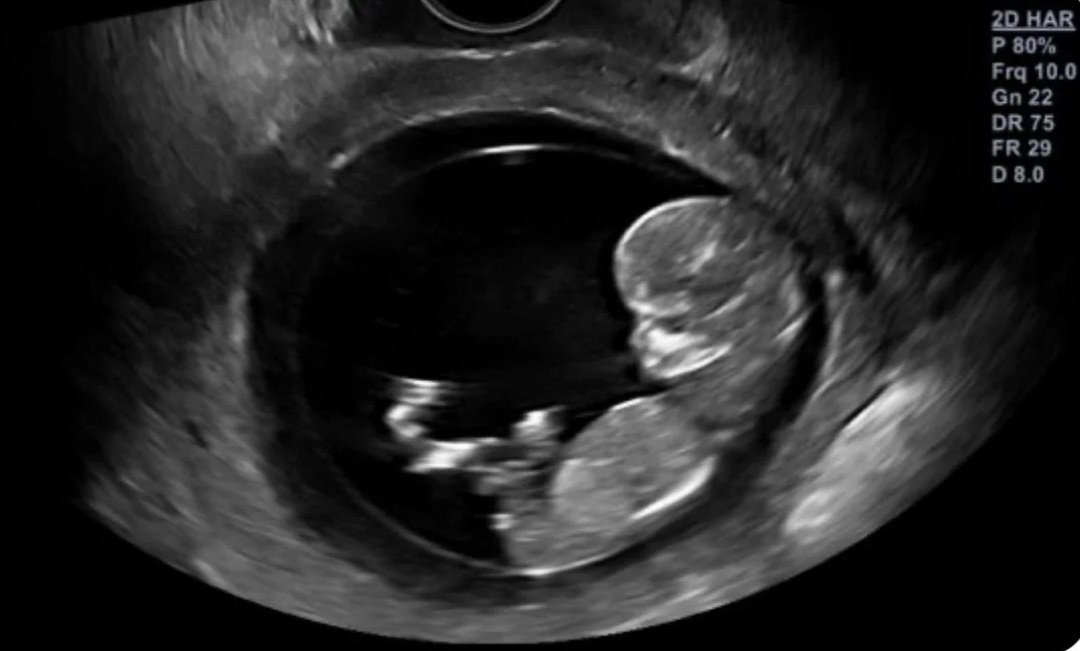

Vitaliteitsecho (week 7–10)

Dit is een vroege echo waarbij we kijken of de zwangerschap op dat moment intact is. We kijken of de zwangerschap zich goed ontwikkelt, of de zwangerschap in de baarmoeder zit en of er een kloppend hartje zichtbaar is.